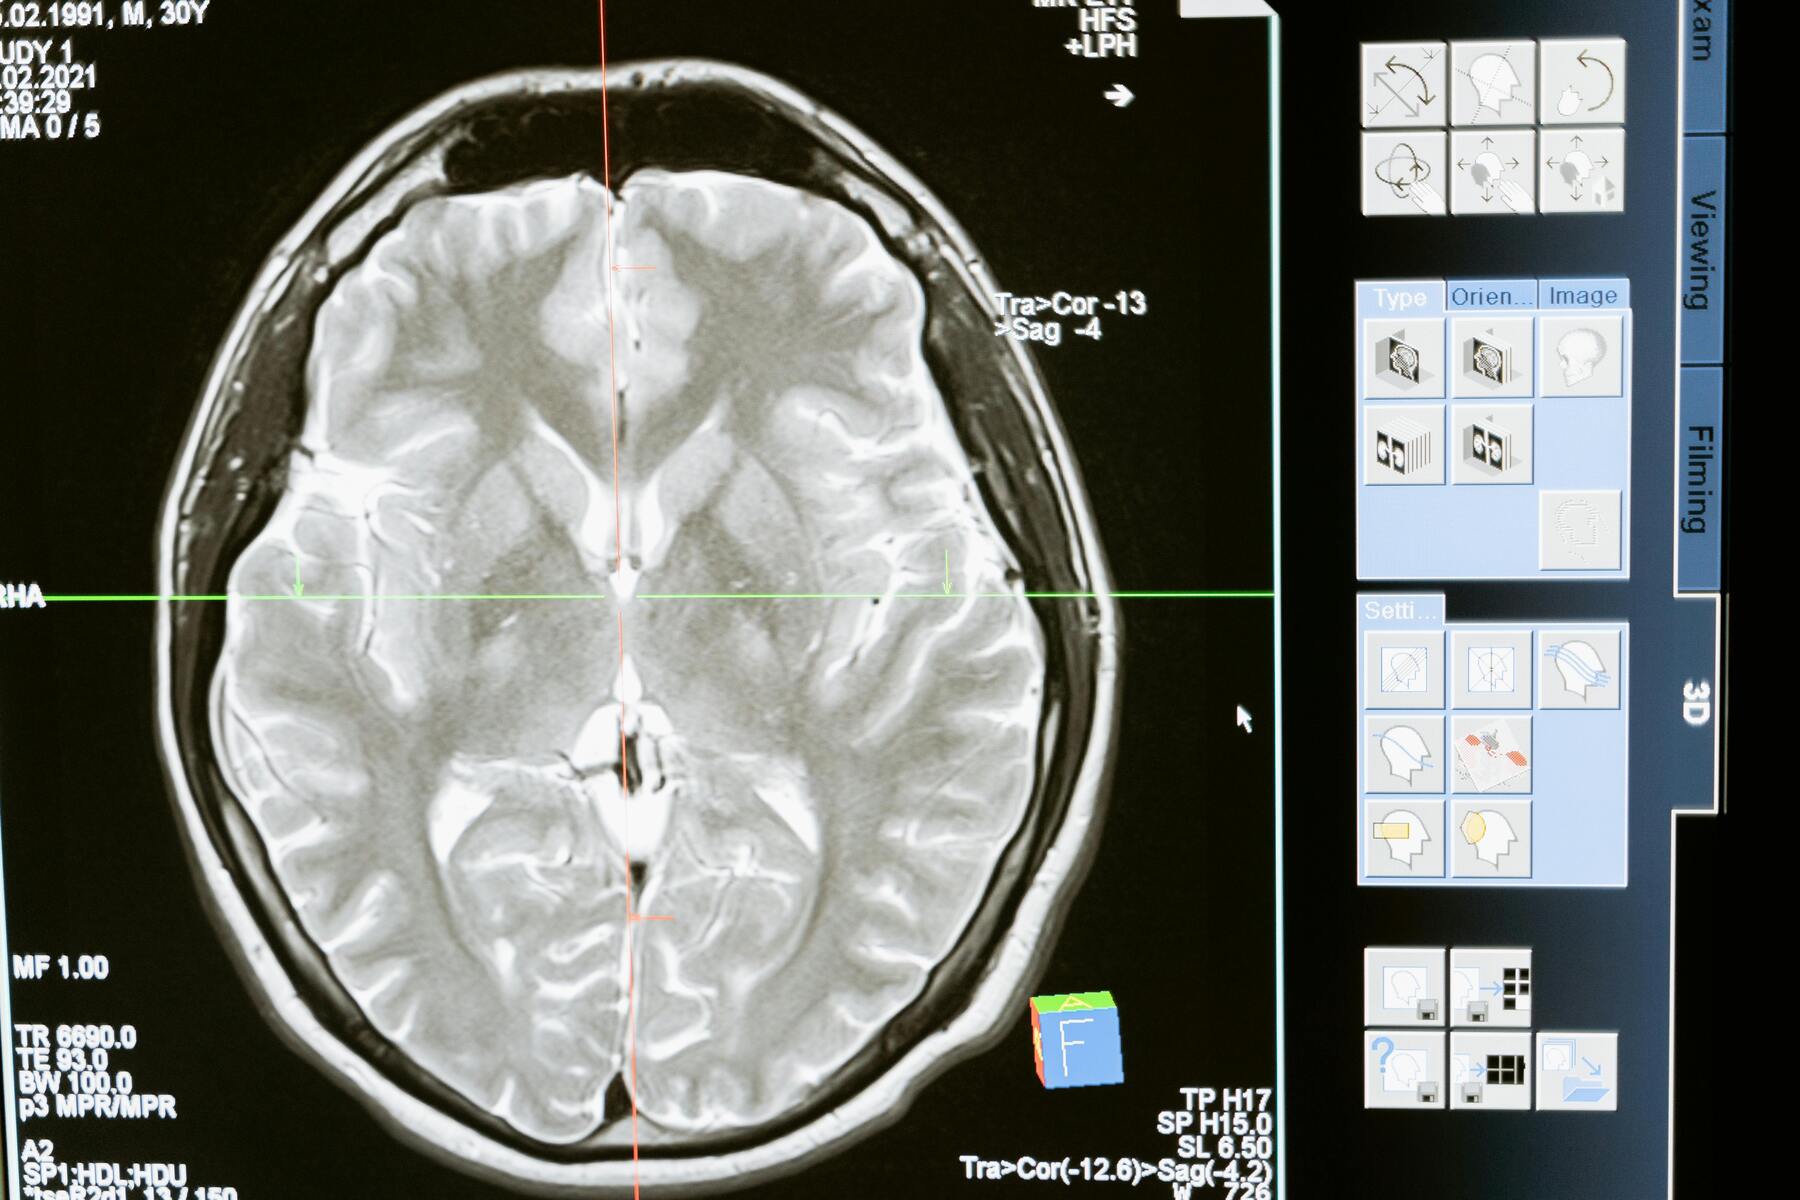

Ett av de tydligaste exemplen på AI:s genomslag inom sjukvården är dess förmåga att identifiera mönster och anomalier i röntgenbilder, MRI-skanningar och andra diagnosticeringstekniker. Företag som Google Health har utvecklat AI-algoritmer som kan upptäcka specifika sjukdomar, som bröstcancer i tidiga skeden, med imponerande noggrannhet. Dessa AI-algoritmer blir kontinuerligt tränade med nya data, vilket gör dem allt bättre på att känna igen sjukdomstecken på bilder.